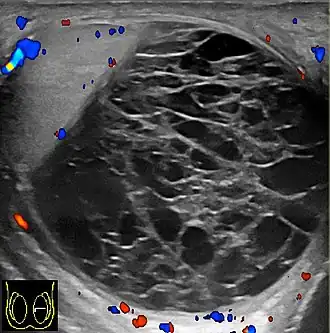

![]() Ecografía escrotal de un hematocele, un par de semanas después de su aparición, como un volumen líquido con múltiples tabiques gruesos. El hematocele no muestra flujo sanguíneo en la ecografía Doppler. Un piocele tiene una apariencia similar, pero fue descartado por falta de inflamación. | ||

El hematocele es un tipo de masa escrotal, caracterizada por una colección de sangre alrededor del testículo y tienden a ser considerablemente dolorosos.[1]

El hematocele es generalmente una lesión aguda consecuencia de trauma testicular—incluyendo posoperatorio—, aunque algunos casos pueden ser idiopáticos.[2] Los casos de hematocele crónicos son menos frecuentes y se deben a desgarros o perforaciones en la túnica vaginal o en la albugínea testicular.[3] El diagnóstico acertado de una masa escrotal es importante para preservar el testículo.